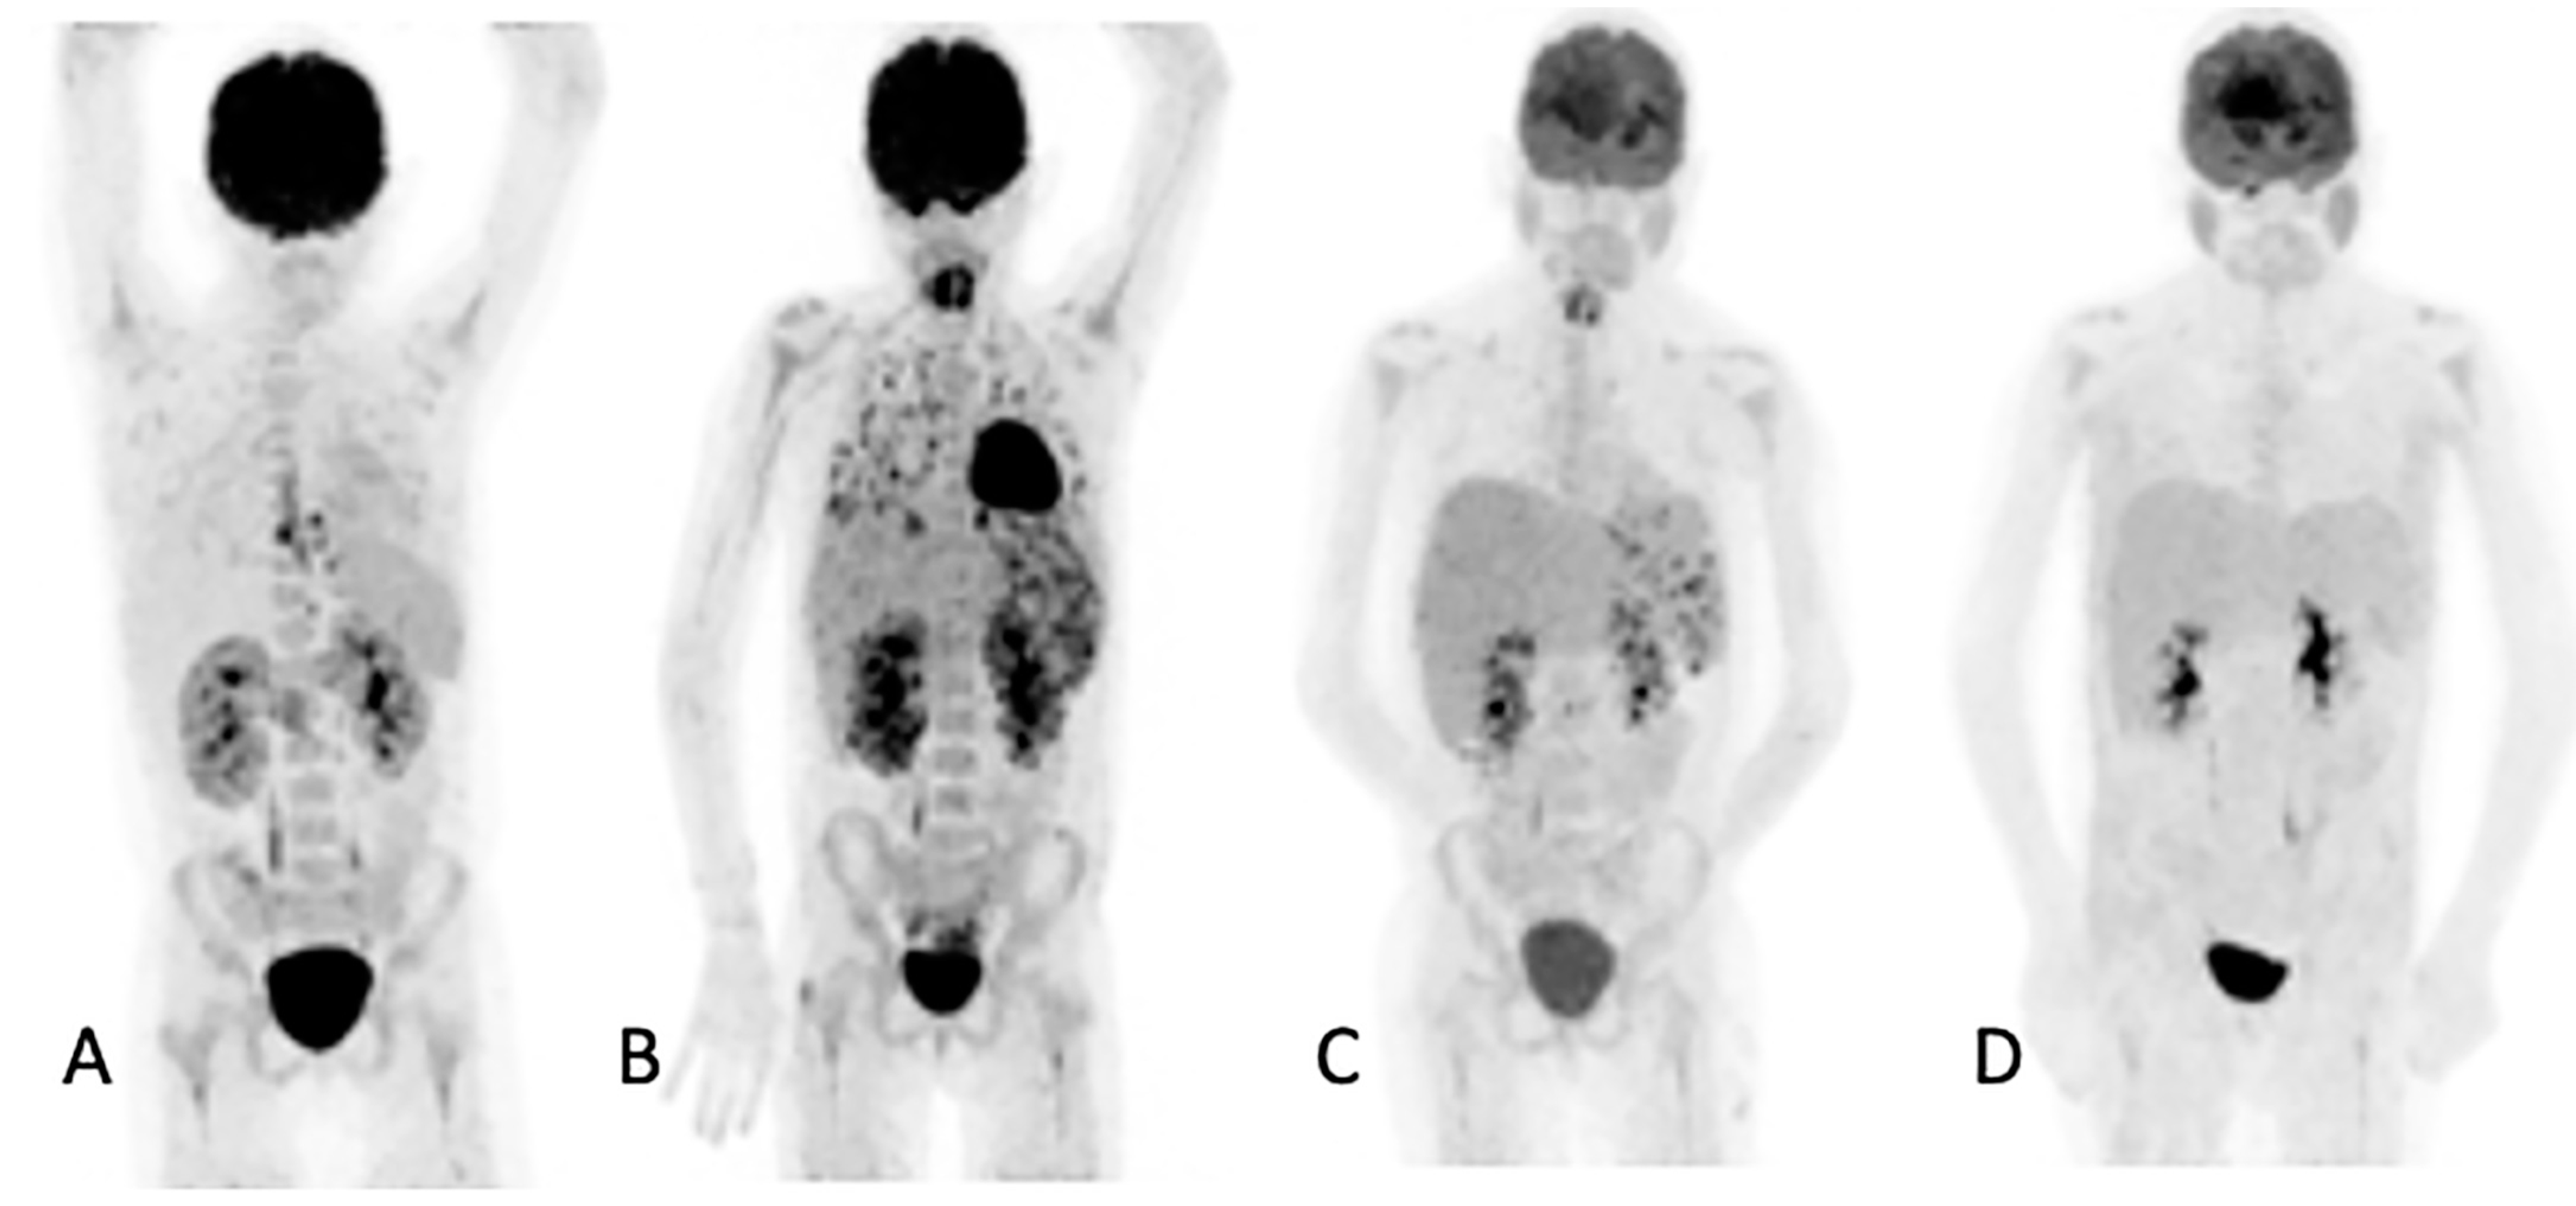

3.5. Added Value Due to the Metabolic Assessment of Lesions by Patient

Figure 3. Ten-year-old female with acute myeloid lymphoma who developed a fever, on chemotherapy, with no response to antibiotics. An abdominal ultrasound demonstrated bilaterally enlarged kidneys. Initial [18F]FDG PET/CT MIP image (A) showed focal metabolic uptake in kidneys, spleen and esophagus. She was started on antifungal treatment, but the fever persisted, and a repeat study (B) showed the worsening of renal splenic lesions with no pulmonary lesions. The antifungal treatment was changed; the fever subsided, and the serum infective markers decreased. A repeat [18F]FDG PET/CT performed after 6 weeks (C) showed resolution of the pulmonary and most of the renal and splenic lesions. The treatment was continued for another month, and a follow-up [18F]FDG PET/CT (D) showed a complete metabolic response that helped the clinician to end the antifungal treatment.